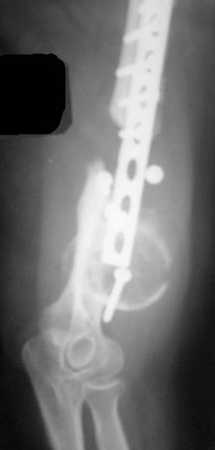

Рентгеновская версия реконструкции. хронология:

после операции, 2 мес. после операции, через 1 год

Движения в полном объеме восстановлены к 2 мес. после операции. Если надо могу показать мультик. Сейчас уже прошло более 3 лет, больная не

показывается. Успехов ЛАФ.